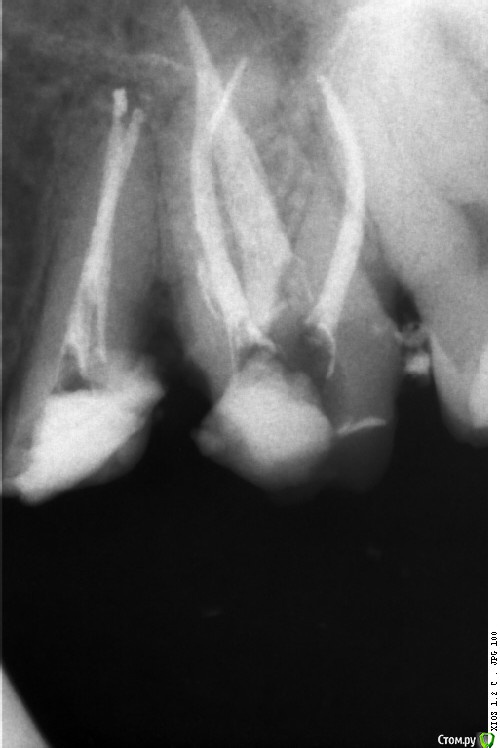

St. Опубликовано 23 марта, 2016 Автор Поделиться Опубликовано 23 марта, 2016 Совсем фейл. Повторное эндо. Сломала на финише профайл 30,04. Вроде обошла 15, но ротари ушла в сторону. Пац обо всем предупрежден. Наблюдаем. Решили не доставать ибо по твердым тканям там и так печаль, если спрямить доступ большая вероятность ленточной перфы. А что бы в таком случае сделали вы? 3 Ссылка на комментарий